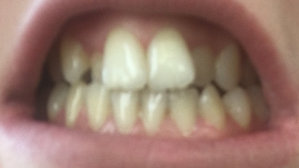

Но хочу у Вас поинтересоваться на всякий случай: что врачи скорее всего будут предпринимать в моем случае? И получится ли у них вообще мне сделать красивую ровную улыбку?

В Вашем случае консультация по переписке некорректна, в связи со сложностью работы. Отсутствие передних зубов (или частичное отсутствие) требует очень тщательного осмотра и составления плана лечения.